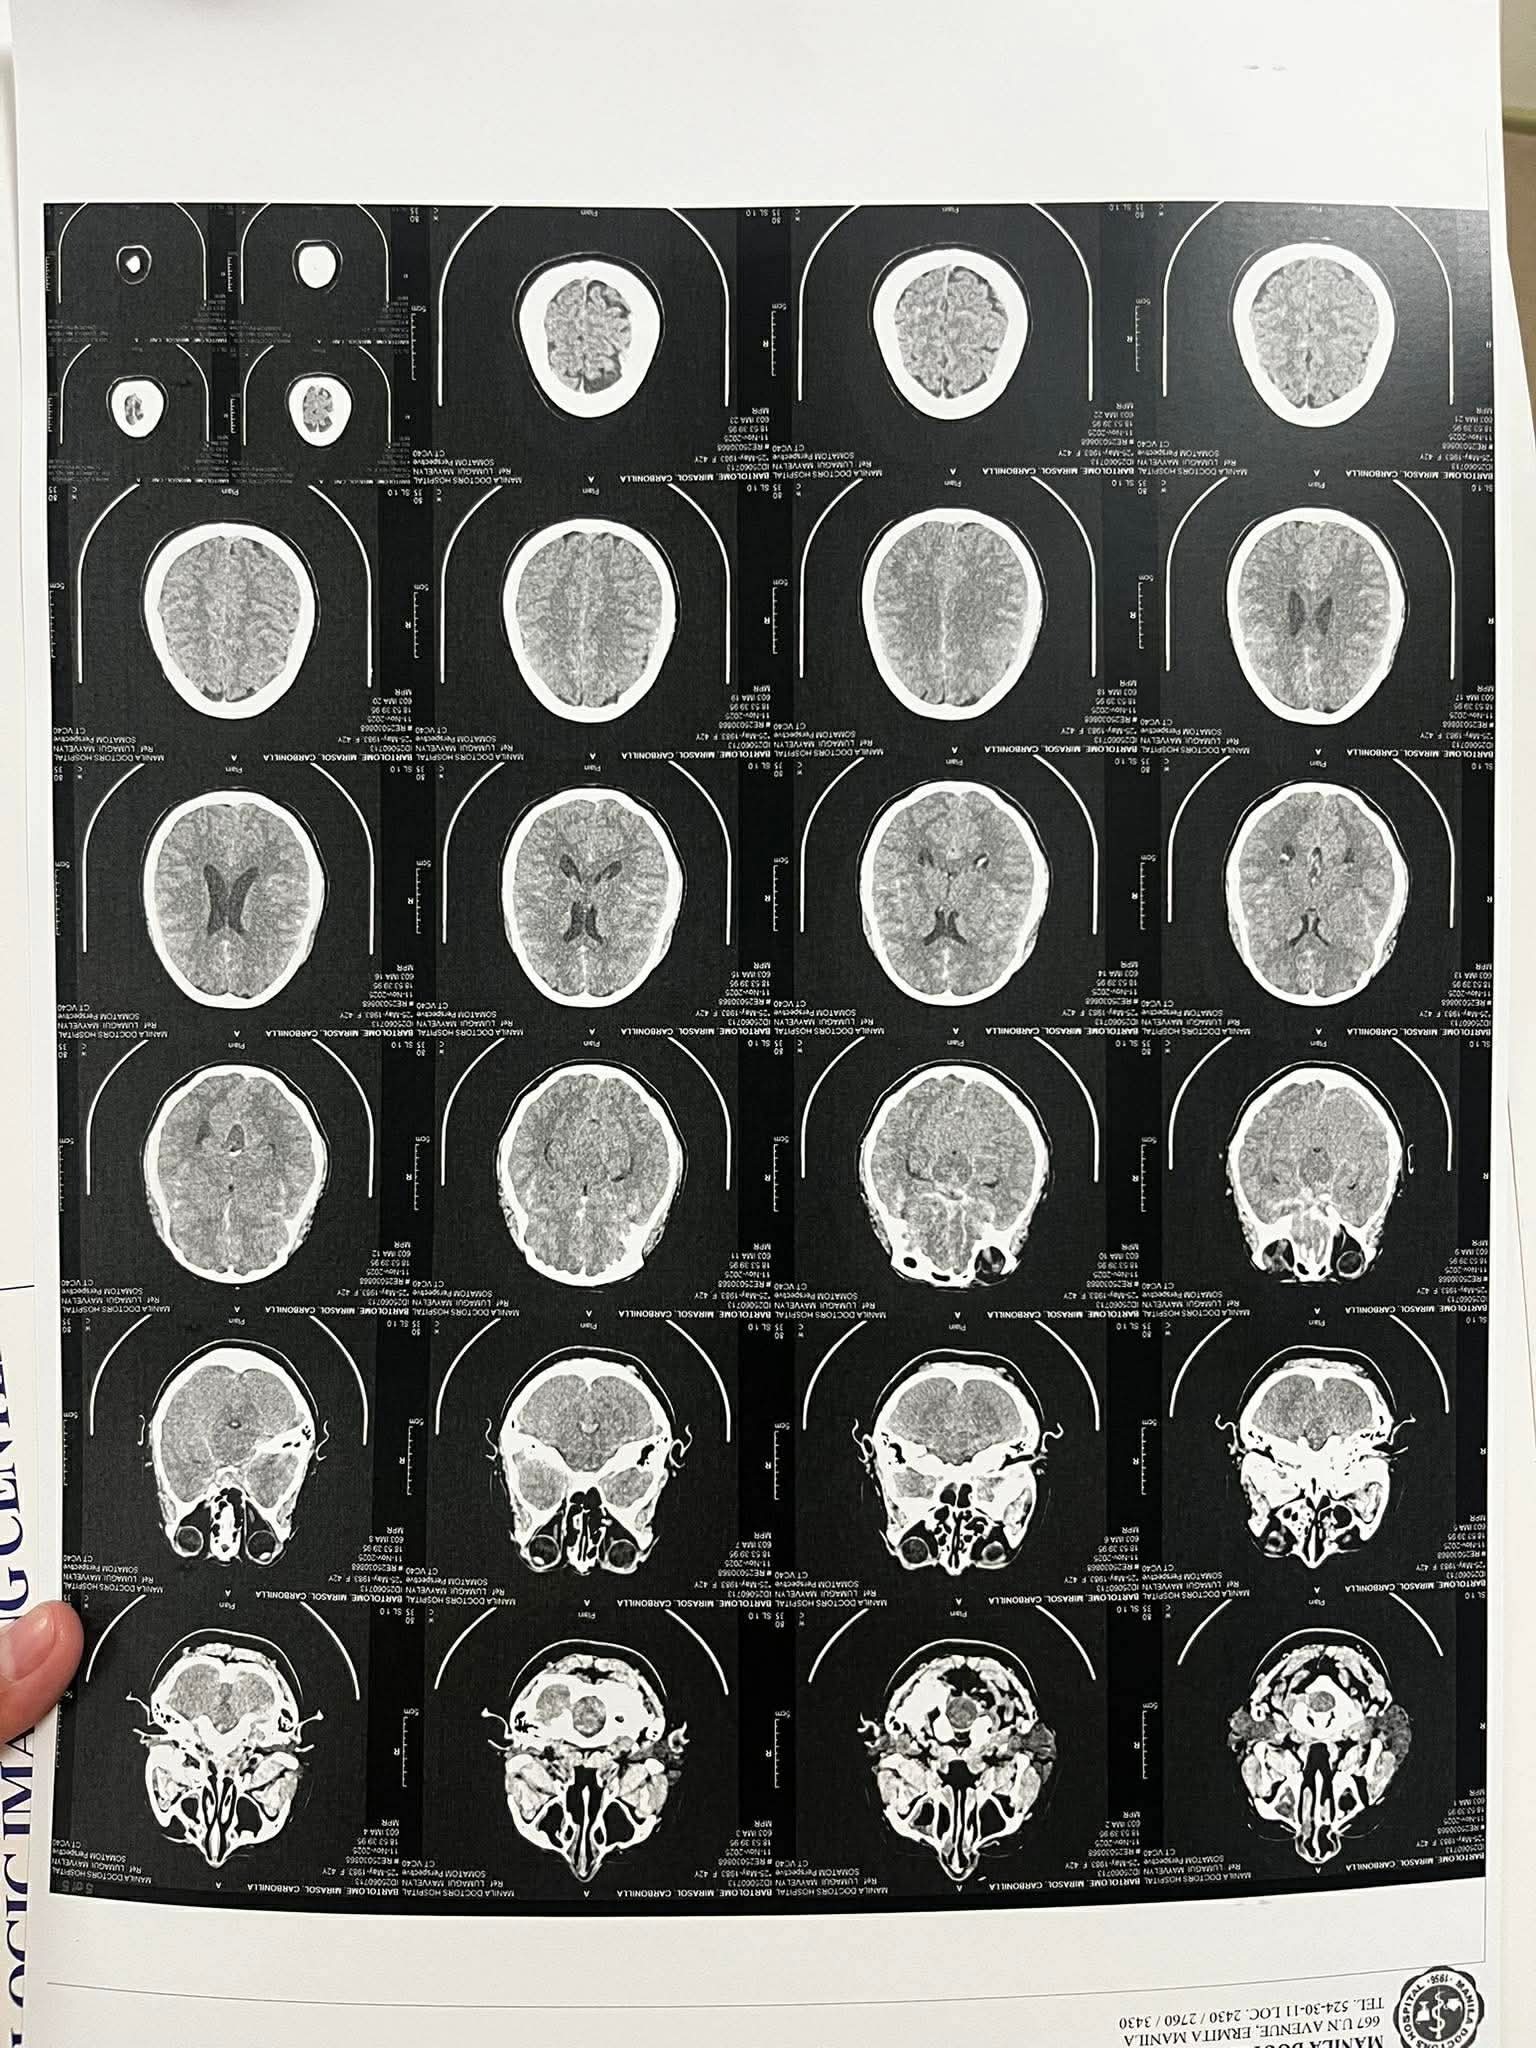

On Tuesday, November 11, 2025, during a short break, Tots woke up feeling the need to use the restroom. Shortly after, she began vomiting and experienced severe head pain. Her colleagues immediately brought her to the PCG clinic, where she was assessed and referred to bring her to the hospital. The nearest hospital is the “The Manila Doctors Hospital” for urgent care.

Recent medical results revealed that Tots suffered an aneurysm. After consulting with her doctors, the family decided on the coiling procedure, which is a common treatment for aneurysms. However, the estimated cost for the procedure ranges from ₱1,500,000 (CAD37,500) to ₱2,000,000 (CAD 50,000), excluding professional fees and hospitalization. Professional fees alone may reach up to ₱500,000 (CAD12,500), and after surgery, Tots will need to stay in the ICU for observation before moving to a recovery room. The family estimates the total cost could reach up to ₱3,000,000 (CAD 75,000).